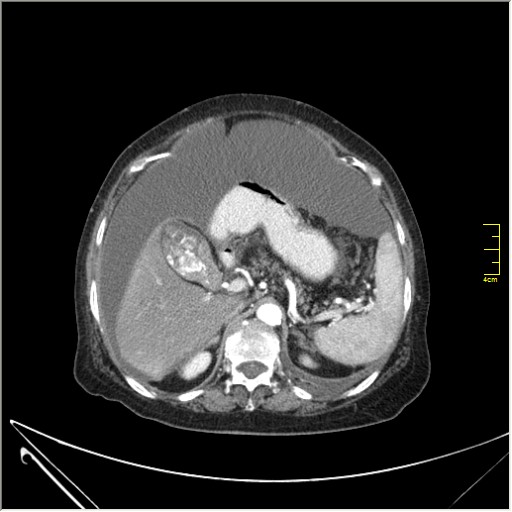

Женщина 72 года. Поступила с жалобами на вздутие живота. После осмотра хирургом, была сразу направлена на КТ брюшной полости.

Итак, асцит с объёмным образованием таза. В данном случае можно быть более конкретным, у пациентки неоплазия правого яичника с региональной лимфаденопатией (увидели?) и выраженным асцитом, характерным именно для злокачественных опухолей яичников. Пациентка оперирована ( операция Вертгейма); диагноз верифицирован: аденокарцинома правого яичника (серозная). Направлена к онкологу для дальнейшего лечения.